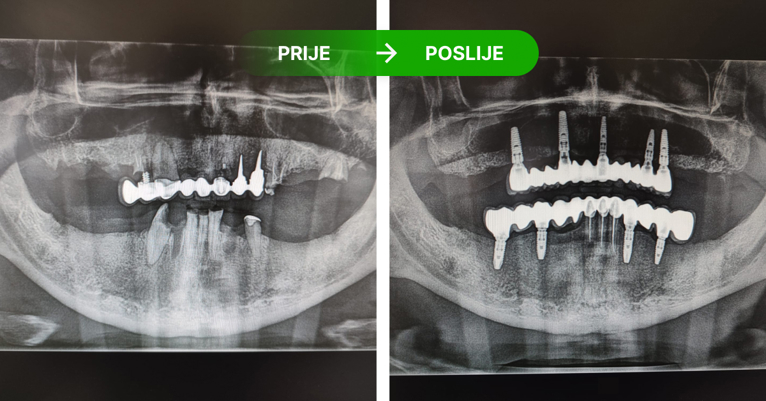

Zubni implantati su titanski vijci koji se ugrađuju u kost kao zamjena za korijen zuba, jednog ili više zuba. Pristup je individualan ovisno o RTG snimci i preostalom broju zuba. Nije potrebno brusiti susjedne zube, već ugrađujemo implantat. Ugrađujemo implantate Nobel Biocare. Ako se održava kvalitetna higijena i kontrola RTG snimanjem implantati traju doživotno, a njihovom ugradnjom zaustavlja se resporbcija kosti.

Dentalni implantati ugrađuju se u čeljust i njihovo učvršćivanje traje 3 do 4 mjeseca – kontrolira se rendgen slikom.

Postupak se izvodi u lokalnoj anesteziji i potpuno je bezbolan. Ukoliko je potrebo ugraditi više implantata, ugrađuju se istovremeno u jednoj posjeti. Nakon 3 do 4 mjeseca vrši se kontrola učvršćivanja i pristupa se izradi keramičkog mosta ili krunice.